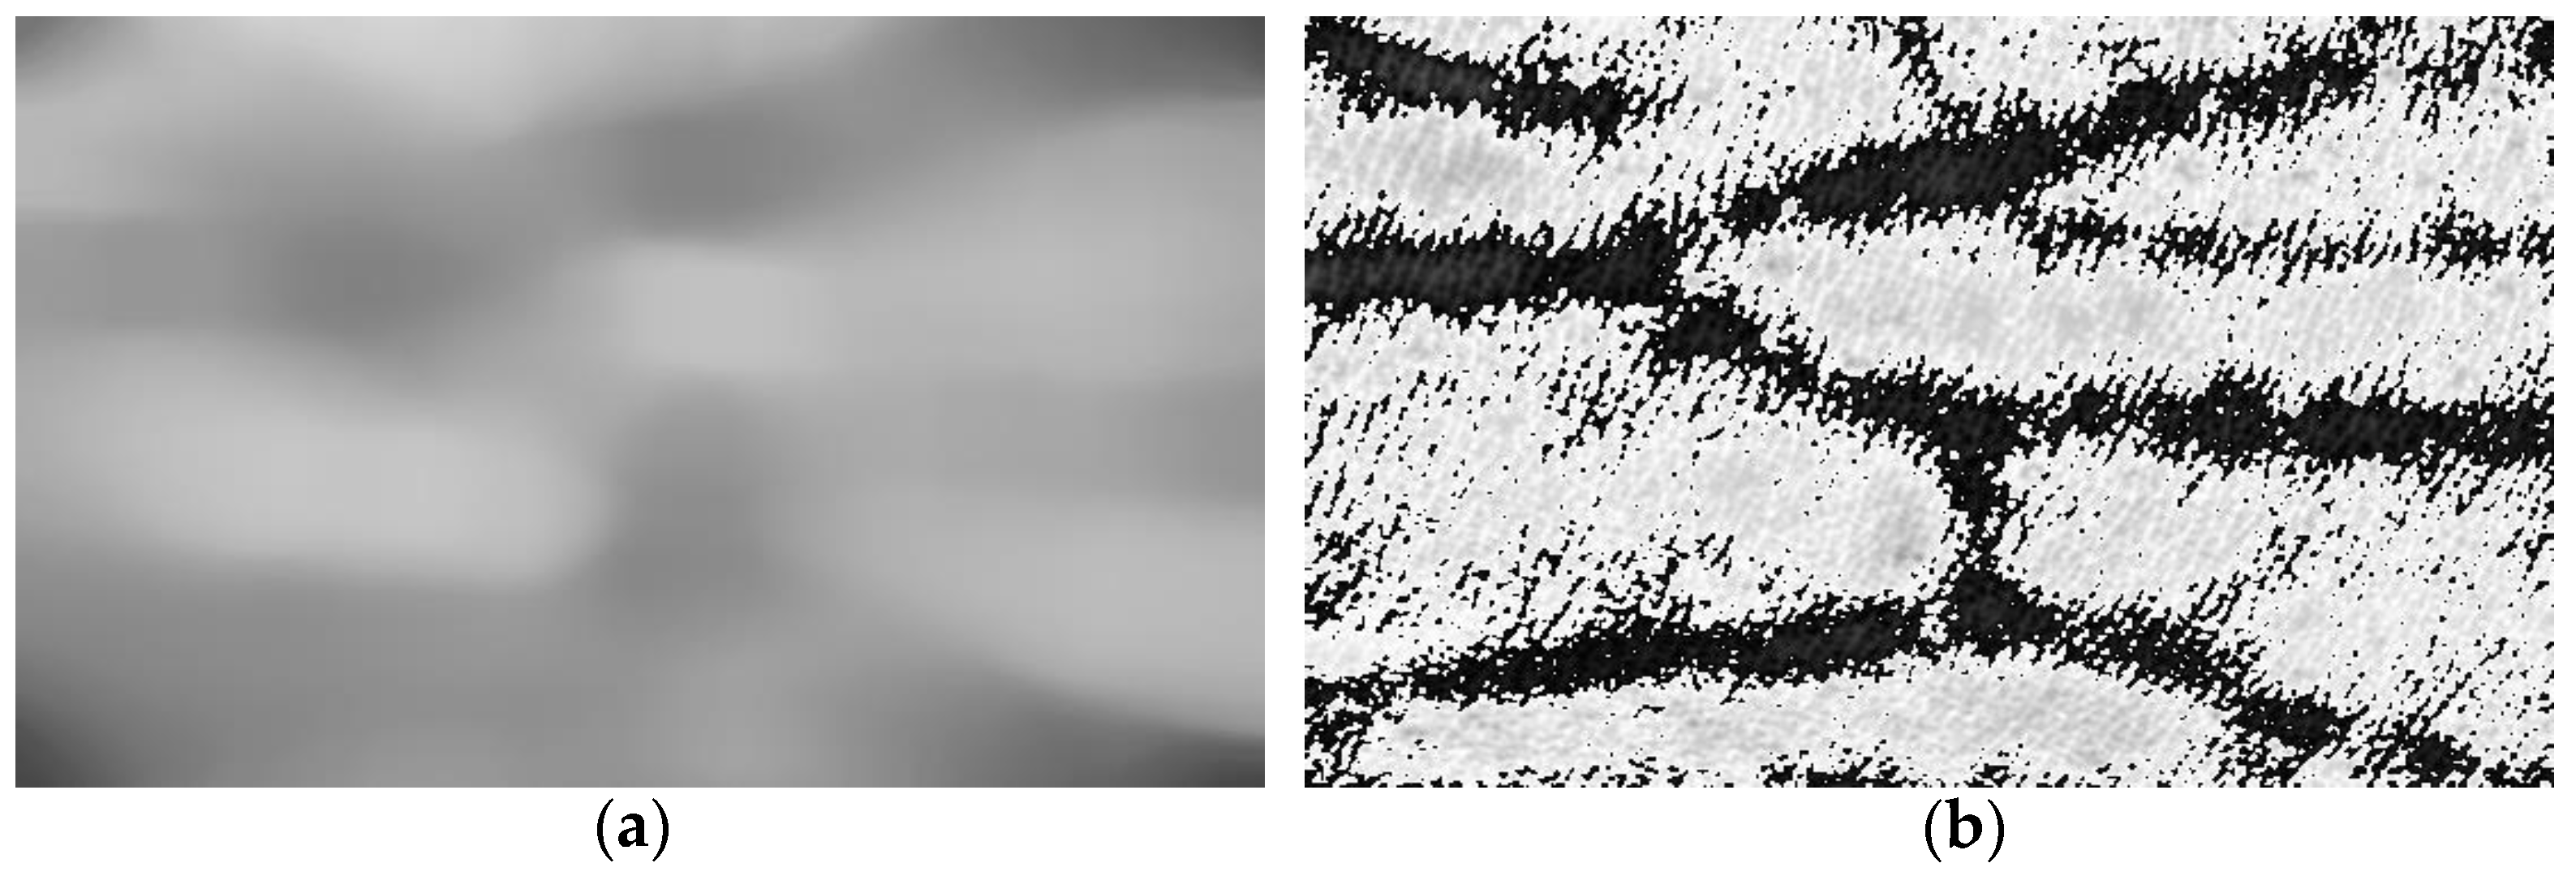

2.2. Vascular Information Extraction and Image Background Subtraction

3.1. Evaluation of Image Enhancement Algorithm